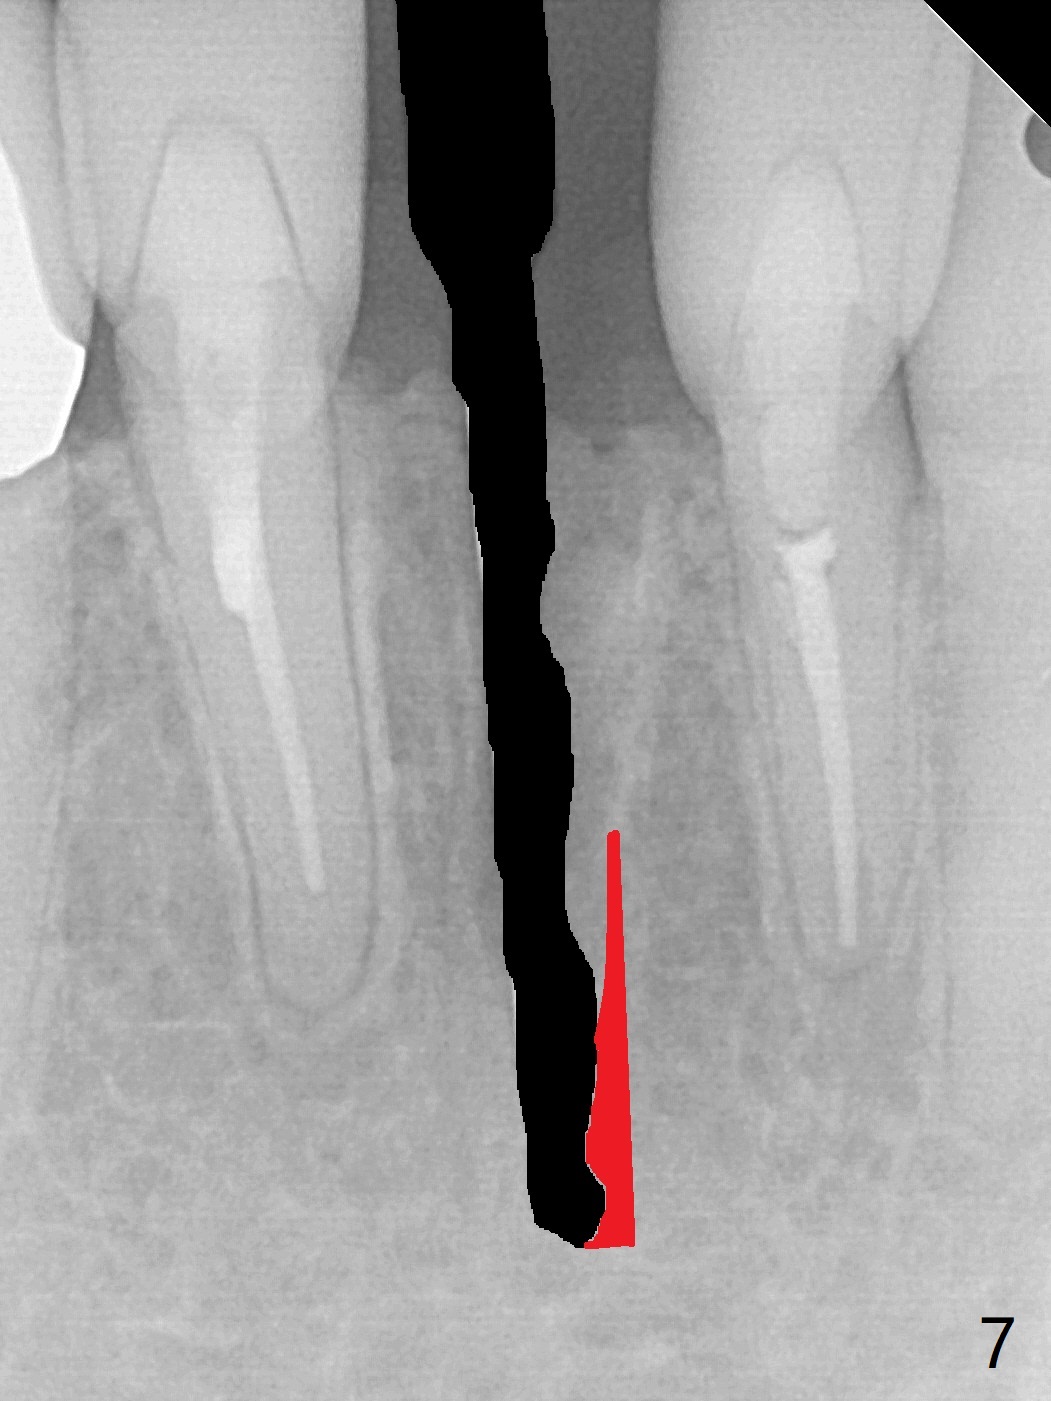

A drawback of implant planning at #25 is not to use a preop PA (Fig.1 (^ fracture line)). The initial trajectory seems to be alright (Fig.2), but a 2.5x14(2) mm implant placed is close to the tooth #26 (Fig.3). In fact the affected tooth is deviated distal; osteotomy should be initiated in the mesial slope of the socket (Fig.4 red line). The final trajectory appears to be perfect (Fig.5). Furthermore the 1st intraop PA should be analyzed carefully (Fig.6). A new osteotomy should be established mesial or the existing one should be moved mesial with Lindamann bur (Fig.7). The distal implant placement may be related to more bone loss in the distal crest 3.5 months postop (Fig.8) and more severe distal papillary recession (Fig.9 *). The bone density increases at the levels of the non-thread and thread portions of the implant (in the original socket) nearly 10 months post cementation (Fig.11 *, <). There is no bone loss 16 months post cementation (Fig.12).